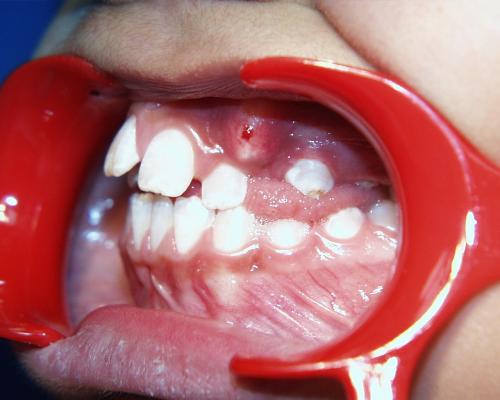

Beim nächsten Fallbeispiel war der Oberkiefer deutlich zu schmal im Verhältnis zum Unterkiefer, der Biß war frontoffen und die oberen Schneidezähne standen sehr unregelmäßig bei einer auffallenden Mittenverschiebung nach links.

Die Zahnbogenmitte wurde eingestellt, die oberen Eckzähne eingeordnet und nach Einbeziehung des unteren Zahnbogens der offene Biß beseitigt.

Ende der aktiven Behandlungsphase

(nach 2 Jahren und 4 Monaten)